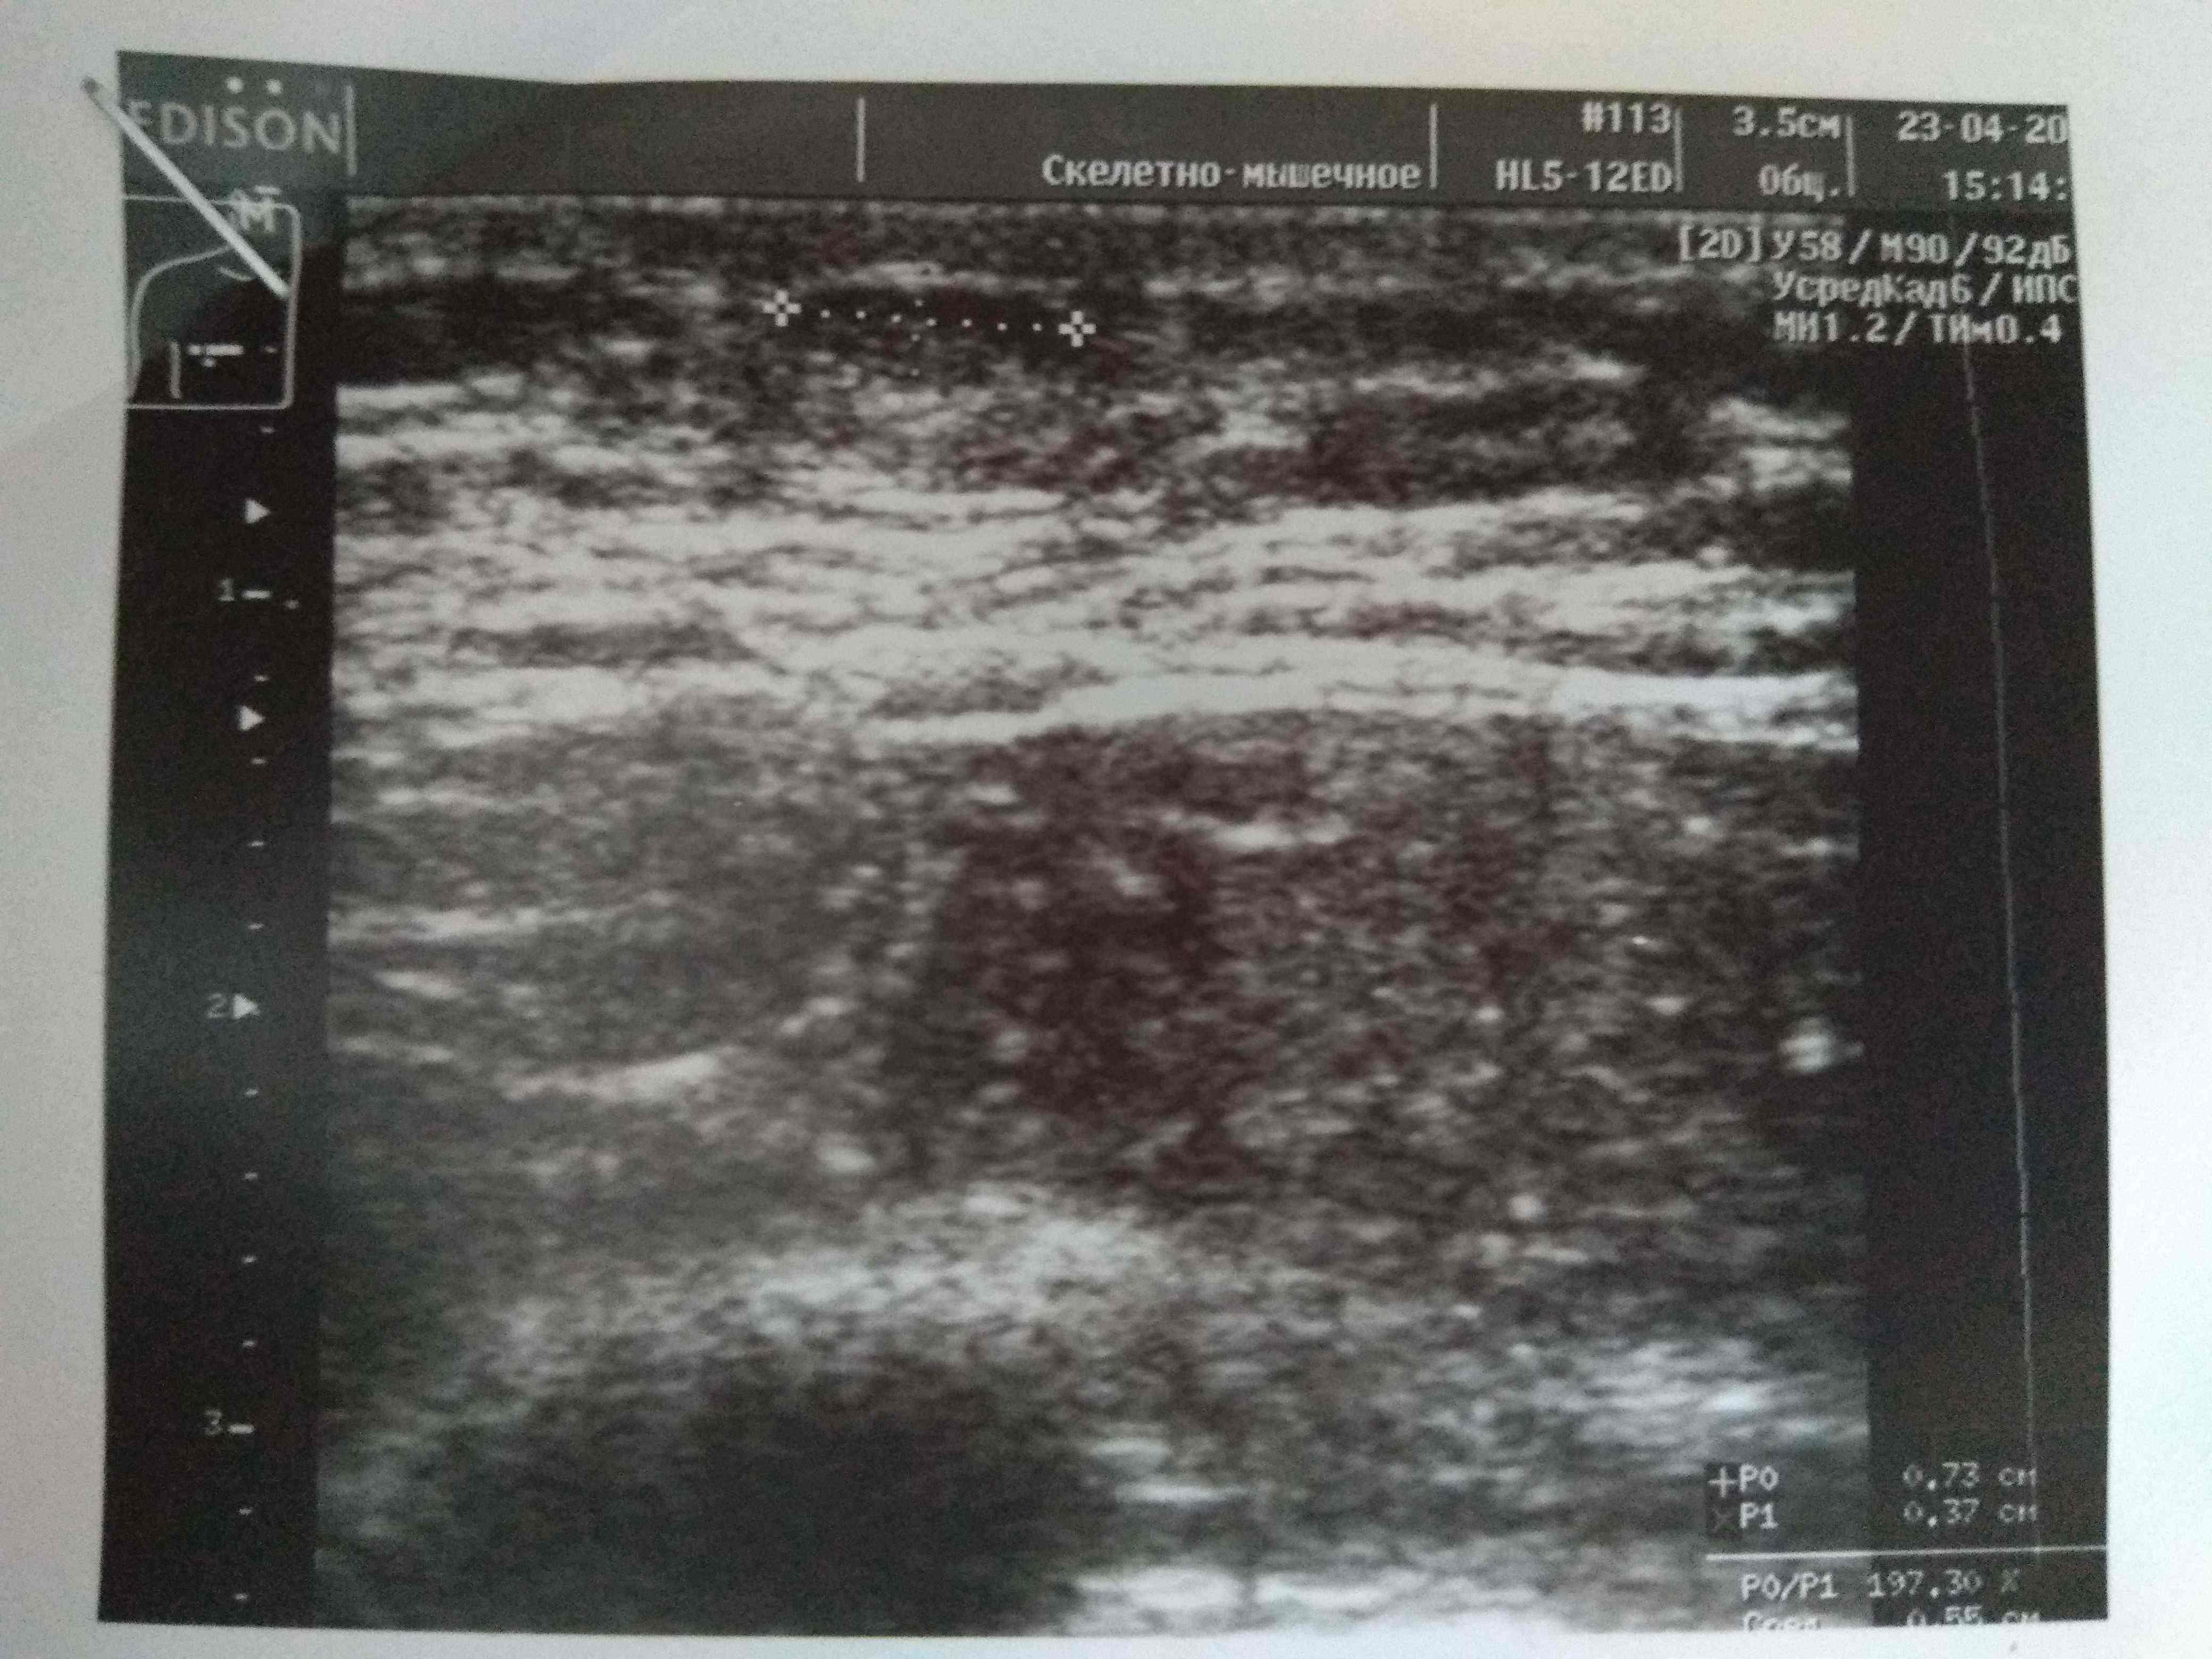

Парни всем доброго вечера! Недавно поднимали вопрос об уплотнении в области сосков на курсах с декой. Суть вопроса что анализы постоянно контролирую как строгая мамка бережет девственность дочки старшеклассницы и они находятся в референсах а уплотнение есть и как будто бы немного растет. Сгонял на УЗИ чтобы расставить все на свои места. В моем случае оно меня порадовало. Думаю что это не единичный случай поэтому и выкладываю инфу сюда. В моем случае гино и не пахло. Имеется небольшое уплотнение состоящее из фиброзно-жировой ткани. Всем здоровья и удачи:swag:

IMG_1400.JPG

Всем привет. Был курс нанфинил100+проп100. Набухли сиськи. Е2 и пролоктин в норме. PartyKill посоветовал сделать УЗИ .Результат: Эхо-признаки двусторонней геникомастии. Ну врачи привыкли всё драматизировать и слегка преувеличивать. Но лечиться всё равно надо. Посоветуйте братья . До этого проблем с гино небыло.Может эта реакция на нанфинил такая? (Юзал первый раз)Хотя дека прошлым курсом нормально так вкатила.Стаж 4 года, ну разумеется с отдыхом , ПКТ, сдачей анализов. Всё по фэн-шую, всё как мы любим.Сейчас идёт мост , энка250 . Хотелось бы подлечиться а с июня снова в бой )) Выручайте

Посмотреть вложение 14714 Всем привет. Был курс нанфинил100+проп100. Набухли сиськи. Е2 и пролоктин в норме. PartyKill посоветовал сделать УЗИ .Результат: Эхо-признаки двусторонней геникомастии. Ну врачи привыкли всё драматизировать и слегка преувеличивать. Ну лечиться всё равно надо. Посоветуйте братья . До этого проблем с гино небыло.Может эта реакция на нанфинил такая? (Юзал первый раз)Хотя дека прошлым курсом нормально так вкатила.Стаж 4 года, ну разумеется с отдыхом , ПКТ, сдачей анализов. Всё по фэн-шую, всё как мы любим.Сейчас идёт мост , энка250 . Хотелось бы подлечиться а с июня снова в бой )) Выручайте

Ну да, железа увеличина.

Давай тогда сделаем как советовал Дон, фарестон по 60 в день на месяц, после месяца сделать УЗИ повторно и посмотреть на динамику